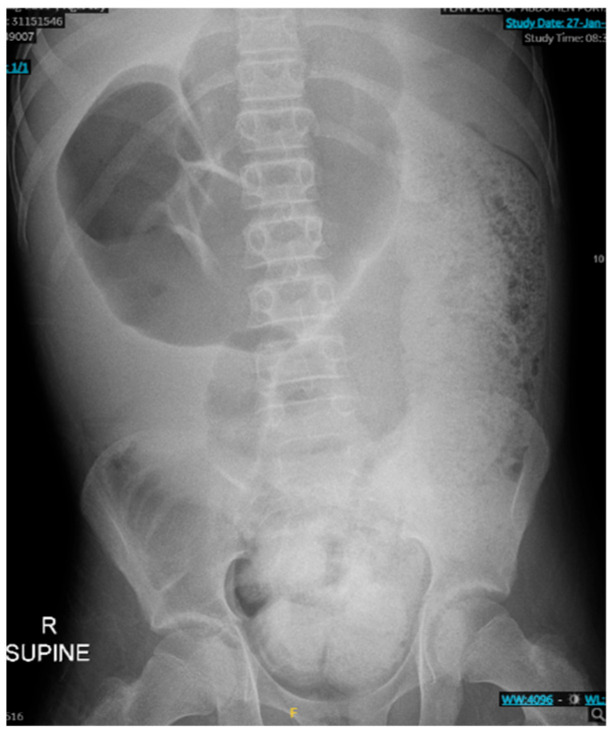

Background and Clinical Significance: Acquired myenteric hypoganglionosis is a rare dysmotility disorder that can present in childhood and adulthood, characterized by a reduced number of ganglion cells within Auerbach's plexus. Due to the rarity of the pathology, few case reports of acquired myenteric hypoganglionosis in adolescents have been described. This case report explores the presentation, risk factors, and surgical complications associated with the ultimate diagnosis of myenteric hypoganglionosis. Case Presentation: We present a case of a 12-year-old male with a history of constipation and achalasia, presenting with constipation and abdominal distention, who underwent a colonoscopy, which was converted to an exploratory laparotomy with loop ileostomy creation due to persistent significant abdominal distention. This was complicated by colonic perforation, most likely secondary to stercoral colitis, requiring takeback to the operating room on postoperative day 11 for an exploratory laparotomy with bowel resection and mucous fistula creation. The patient was then referred to Boston Children's Hospital for motility studies, which revealed poor colonic motility and plans to reassess motility in 1 year. Conclusions: Although rare, it is important to have high clinical suspicion for acquired myenteric hypoganglionosis in children, especially males, with severe constipation.